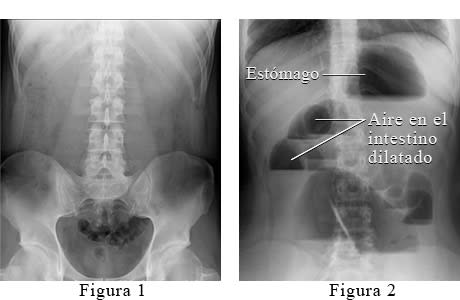

La Figura 1 muestra un abdomen normal. La Figura 2 muestra aire atrapado en los intestinos porque los gases, líquidos o alimentos no pueden pasar normalmente por los intestinos.